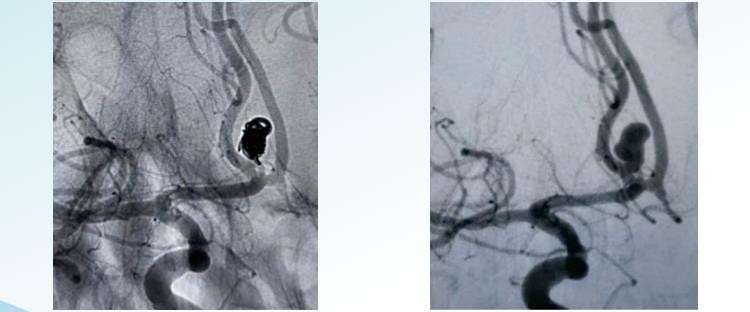

RenovaTMdetachable aneurysm coiling system muaj random, helical thiab 3D detachable xaiv rau endovascular embolization nyob rau hauv diameters ntawm 1 mus rau 22 m. Nws yog tsim los embolize aneurysms los ntawm thav duab kom tiav thiab suav nrog coils zoo li tshwj xeeb kom ua tiav concentric aneurysm filling thiab coils ntawm cov ntim loj kom ua tiav cov ntim ntim siab. Random coiling yog qhov yooj yim tshaj plaws thiab qub tshaj plaws ntawm cov txheej txheem aneurysm coiling. Nws koom nrog kev ntxig ntawm ib lub kauj lossis ib pawg ntawm cov coils rau hauv cov hlab ntsha. Cov coils feem ntau yog ua los ntawm platinum thiab nyias thiab nruj nreem coiled kom tsis txhob muaj qhov khoob lossis qhov chaw los ntawm kev tsim hauv lub hnab. Helical coiling suav nrog kev siv cov hlau ntev dua, nyias nyias uas yog coiled nyob ib puag ncig nws tus kheej hauv helical yam, tsim lub caij nplooj ntoos hlav- zoo li cov qauv. Cov hlau yog muab tso rau hauv lub aneurysm nyob rau hauv ib tug straightened daim ntawv, thiab ib zaug nyob rau hauv, nws raug tso cai rau coil thiab nthuav mus sau lub aneurysm sac. Helical coils yog dav dua thiab zoo dua ntim ntau dua li cov coils random, yog li muab qhov zoo dua occlusion ntawm qhov aneurysm. Lub 3D coil suav nrog kev siv cov kev cai -tsim coil, uas yog tsim los siv cov txheej txheem kev siv tshuab computer uas tsim kom muaj qhov tseeb peb - qauv ntawm qhov aneurysm. Lub kauj yog tsim los kom phim qhov loj thiab cov duab ntawm qhov aneurysm. Hom coil no yog tsim los kom haum snugly rau hauv lub hnab aneurysm, muab occlusion zoo heev thiab txo qhov kev pheej hmoo ntawm cov teeb meem . 3D coils yog tshwj xeeb tshaj yog zoo nyob rau hauv kev kho mob aneurysms uas nyuaj mus cuag los yog nyob rau hauv cov hlab ntsha tawg.

RenovaTM3D Detachable Coils

RenovaTMHelical Detachable Coils